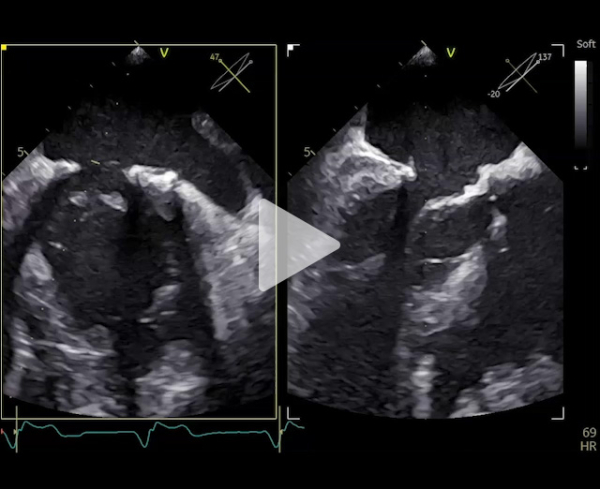

Nouvelle évaluation globale : ETT - ETO

Vidéo 2

- Ventricule gauche dilaté 87 ml/m2, FEVG 79%.

- Oreillette gauche dilatée 55 ml/m2

- Valve mitrale : plastie mitrale sur valve barloïde, insuffisance mitrale de grade 3

- Restriction au niveau de P3

- SOR 30 mm2, VR 54 ml, PISA 8 mm

- Rapport ITV 1,8, onde E 1,8 m/s

- Pas de reflux dans les VP

- Gmoy 6 mmHg

- Fonction ventriculaire droite altérée

- Forte probabilité d’HTP